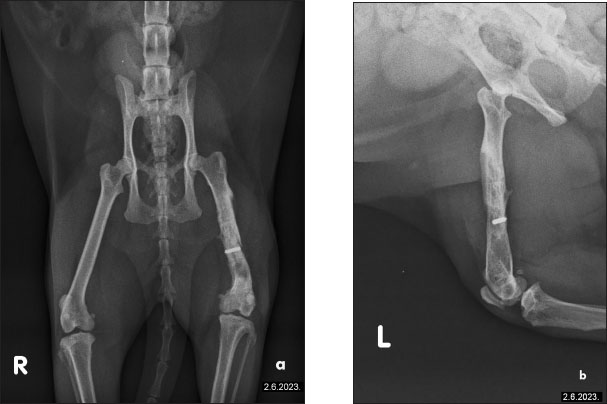

The owner reported continuous improvement, noting that the cat is increasingly bearing weight on the left hind limb, showing fewer signs of pain, and displaying an improved disposition. Follow-up radiographs revealed improvement in the condition of the femur post-therapy (Fig. 4). There is a noticeable improvement in bone structure, indicating enhanced healing and remodeling processes. After 2 months of intensive therapy and visible clinical improvement, the intervals between treatments were further extended. The radiograph shows the bone structure to be more consolidated, indicating effective recovery and remodeling (Fig. 5). Overall, the imaging suggests a positive outcome following treatment. In agreement with the owner, the treatments have continued on a monthly basis, and the cat continues to show progress.

Fig. 5. Radiographic evidence of consolidated bone structure and reduced medullary transparency following 25 sessions of LT.